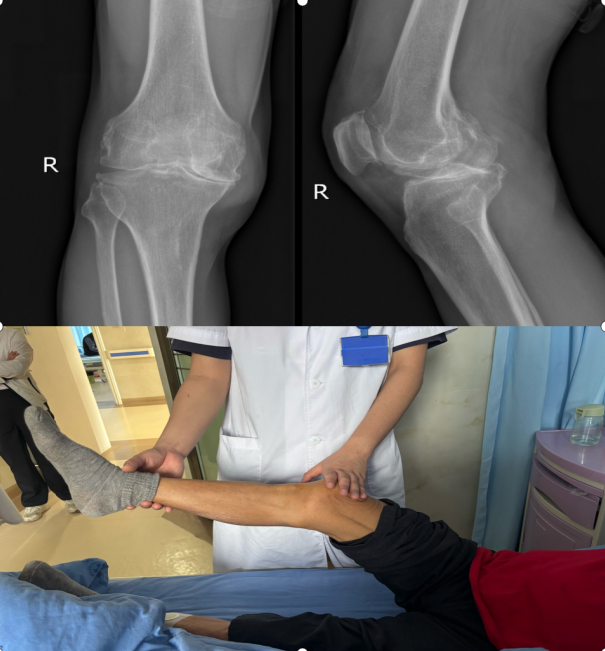

3:哪些膝关节骨关节炎适合PRP治疗?

膝关节采用单点关节腔注射,并根据需要决定疗程。对于PRP非手术治疗膝骨关节炎,建议每次注射量为3-4ml,必要时可间隔2-3周重复注射,每个疗程一般可达3次。